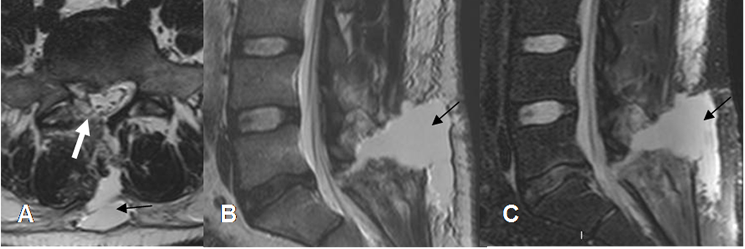

Fig 207 C. Seroma.

A: RM axial en T2, B: RM sagital en T2 y C: RM sagital en STIR. Signos de laminectomía derecha, por hernia de disco en A. Se encuentra colección líquida en los tejidos blandos, por la formación de seroma.